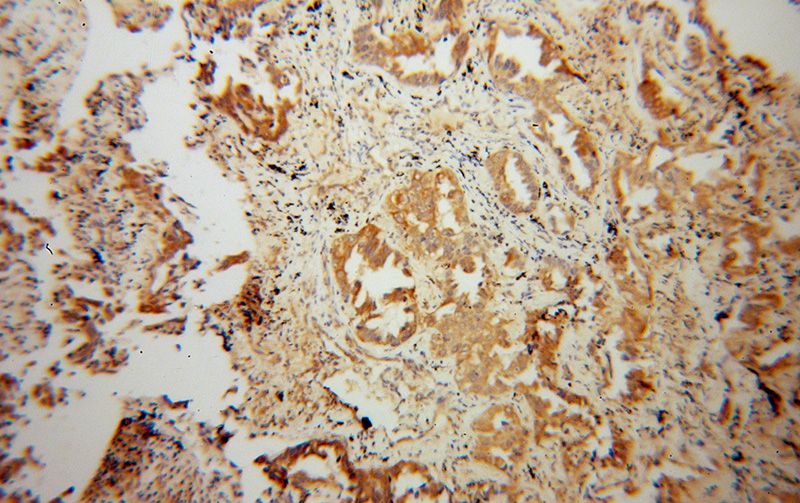

Immunohistochemical of paraffin-embedded human lung cancer using Catalog No:112529(MFN1 antibody) at dilution of 1:100 (under 10x lens)